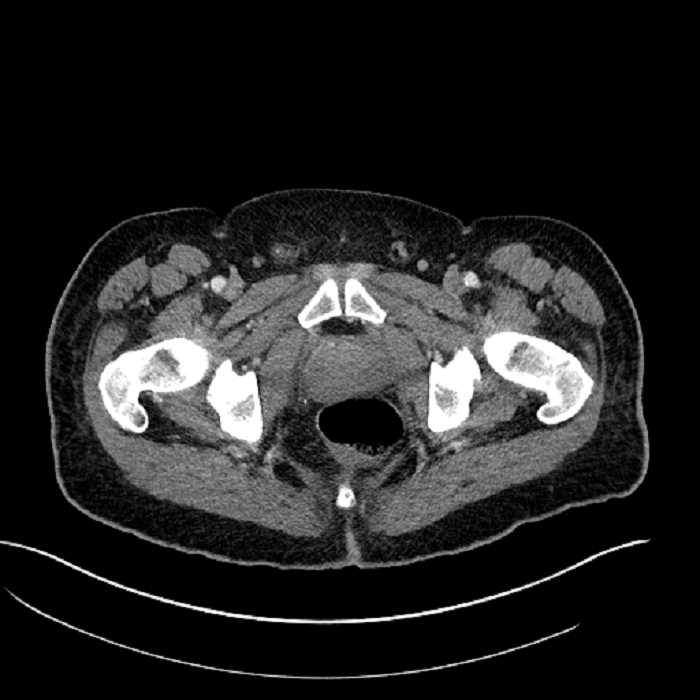

• High grade stenosis of the left common iliac artery, with the left internal and external iliac arteries remaining patent

High grade stenosis of the left common iliac artery. The left external and internal iliac arteries are patent.